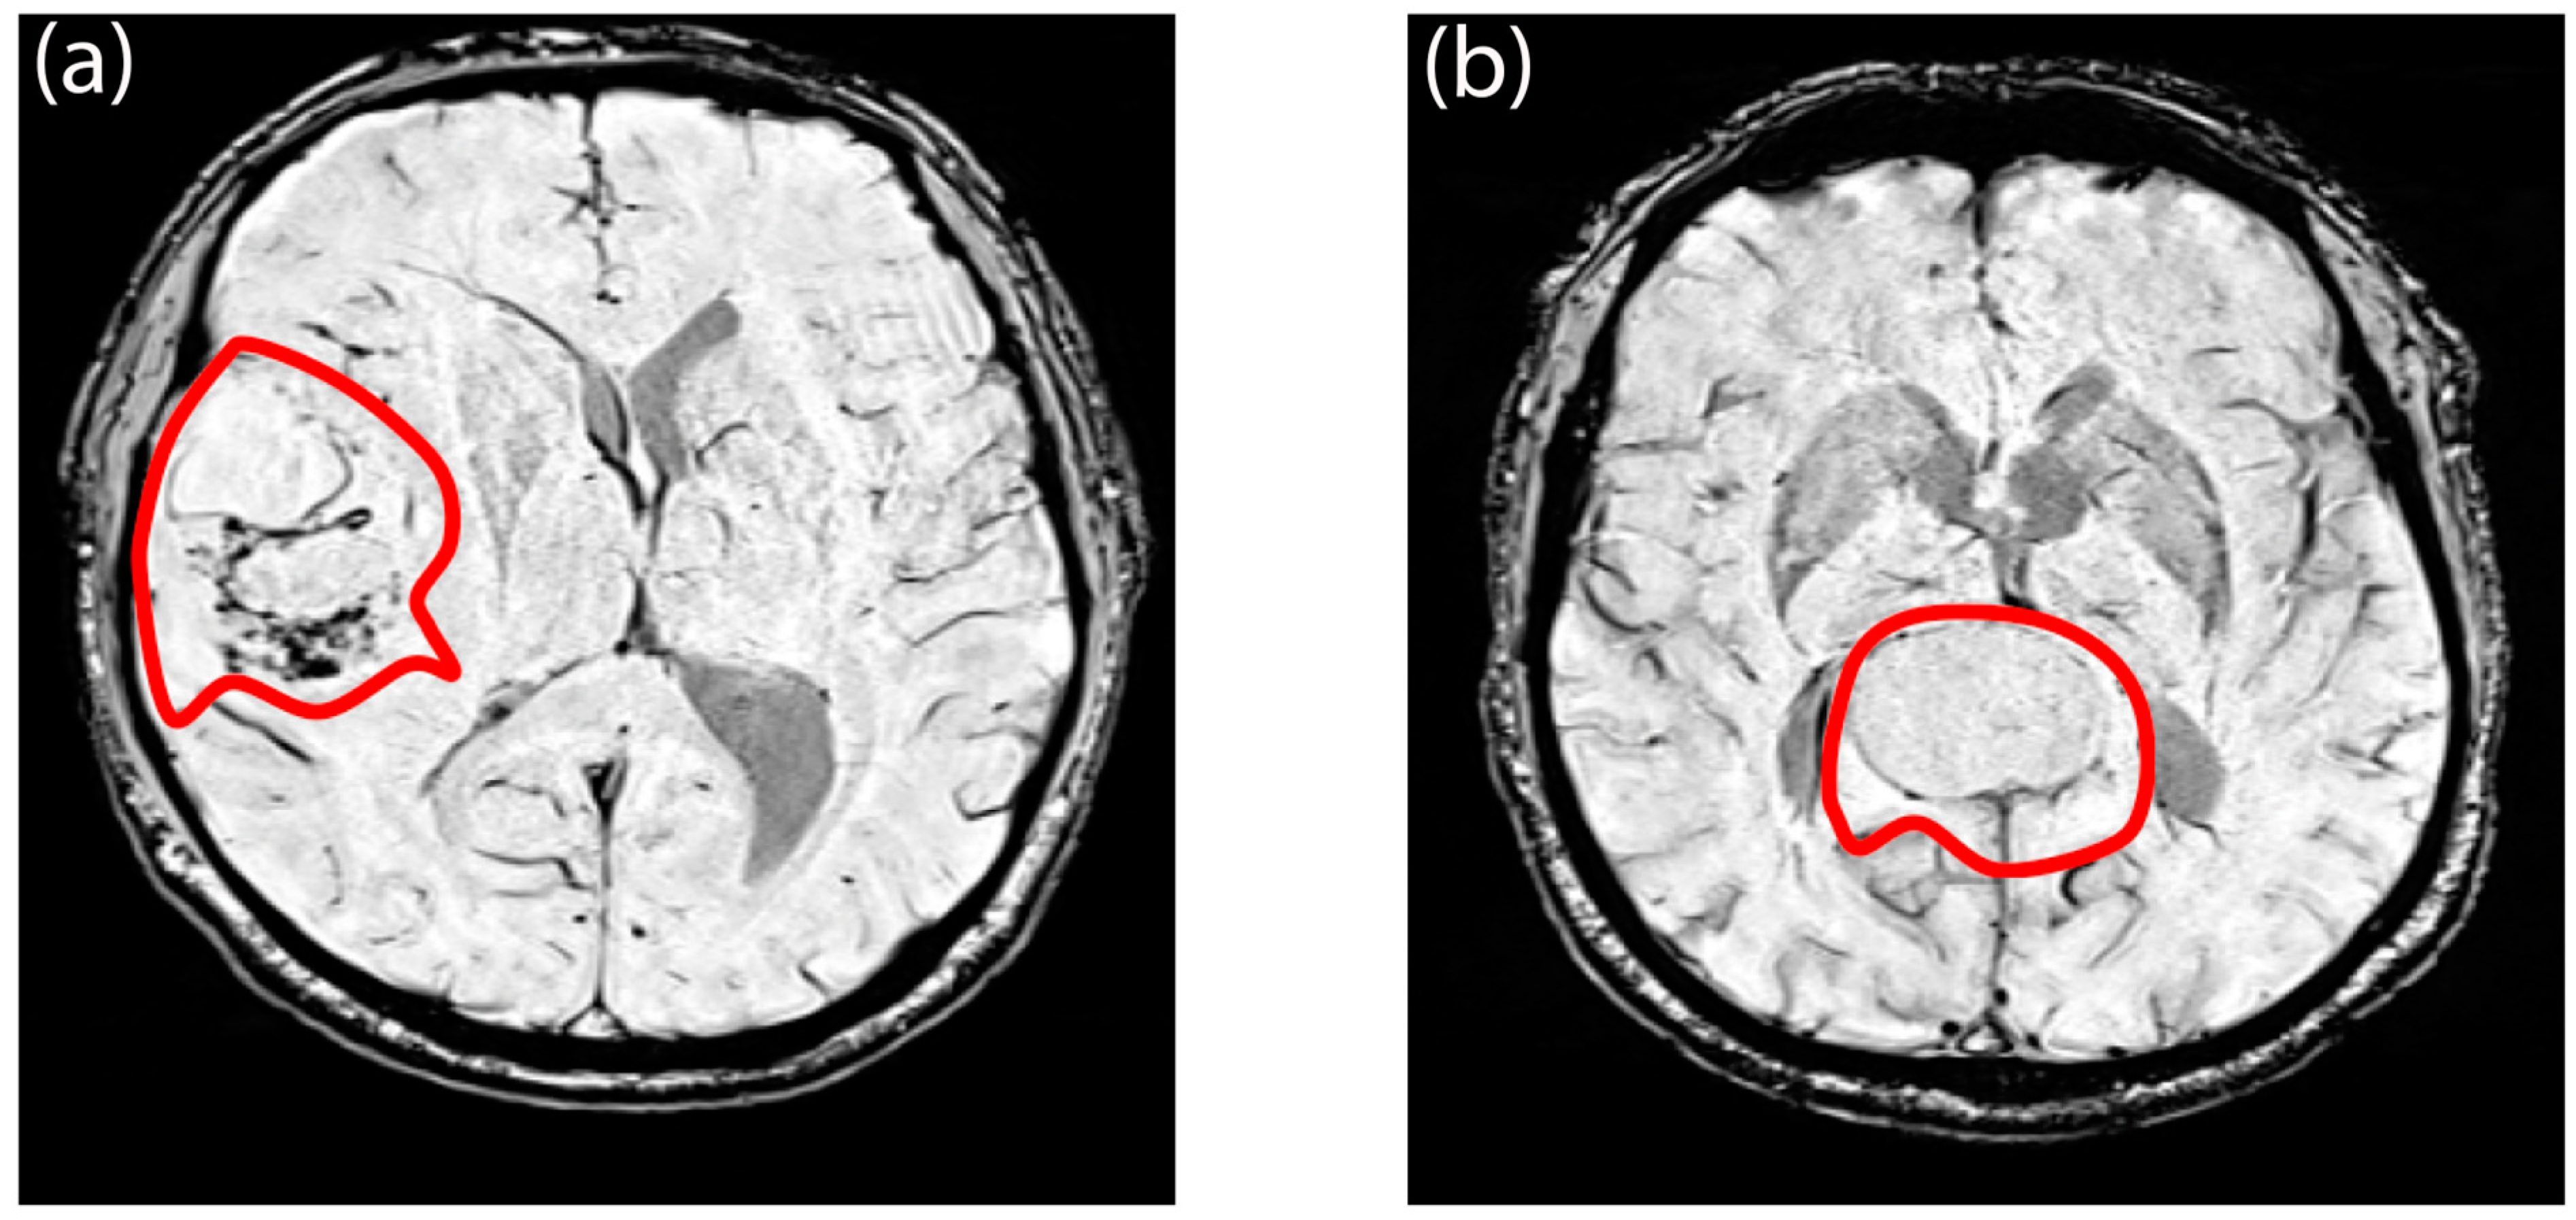

2.5. Image Processing